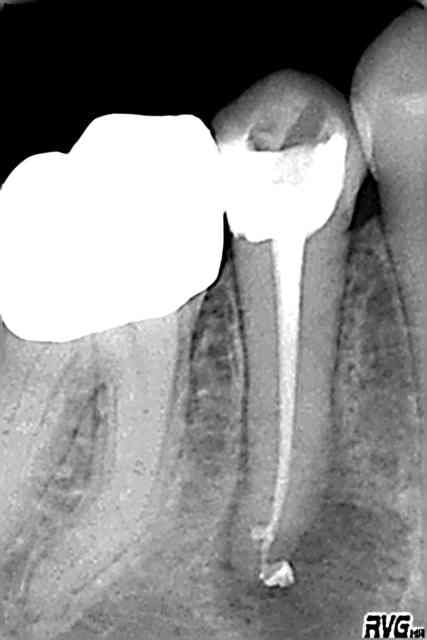

patiente en urgence la semaine dernière

douleurs sur 45 traitée en 2004 (à peu près correctement je trouvais mais sans digue et probablement pas assez hypoclorisée)

ttt repris ce jour(inutile de s'extasier ou critiquer,c'est une reprise lambda)